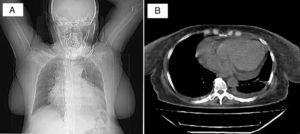

Caso 3Paciente femenina, de 50 años de edad, hipertensa, diabética, con insuficiencia renal terminal en diálisis peritoneal quien consultó por dolor torácico tipo punzada, no irradiado, asociado a disnea de pequeños esfuerzos y dolor abdominal difuso, con fallo en la ultrafiltración (<1L/día) en la última semana. A su ingreso FC: 112 lat/min, FR: 36 ven/min, PA: 140/100mm Hg., °T: 37°C. Consciente. Sin ingurgitación yugular con ruidos cardíacos rítmicos sin soplos y disminución del murmullo vesicular en la base pulmonar derecha. El abdomen blando con dolor a la palpación en epigastrio, sin irritación peritoneal. La radiografía del tórax reveló cardiomegalia y derrame pleural derecho (fig. 1.A). El catéter de drenaje se posicionó en la fosa ilíaca izquierda y pelvis con adecuado patrón de distribución gaseosa intestinal en la radiografía de abdomen. El ecocardiograma documentó derrame pericárdico grande de 1.000ml con colapso auricular derecho y ventricular derecho; movimiento asincrónico del septum interventricular y función sistólica normal del ventrículo izquierdo con FE del 71%. La tomografía del tórax mostró derrame pericárdico grande y derrame pleural bilateral pequeño (fig. 1.B). Se le practicó ventana pericárdica con la que se drenaron 1.000ml de líquido; la biopsia informó tejido fibroso con ligero infiltrado inflamatorio crónico no granulomatoso. No se observó malignidad. Se inició hemodiálisis al identificar la uremia como causa del derrame pericárdico. La evolución fue satisfactoria y continuó manejo ambulatorio por Nefrología.

(A) Radiografía del tórax PA en la que se observa aumento marcado de la silueta cardiaca. No hay compromiso del parénquima pulmonar. No se visualiza el seno costo-diafragmático izquierdo. (B) Tomografía del tórax que registra derrame pericárdico grande circunferencial y derrame pleural bilateral pequeño.